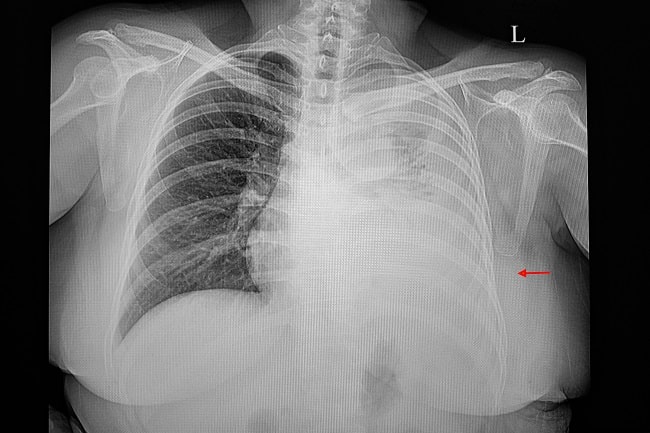

Efusi pleura masif adalah akumulasi cairan berlebih yang mengisi ruang antara pleura viseral dan pleura parietal. Cairan efusi sering mengandung sel-sel keganasan, karena efusi pleura masif umumnya disebabkan oleh proses inflamasi yang dipicu keganasan. Sejumlah keganasan yang dapat mengakibatkan efusi pleura adalah kanker paru, kanker payudara, kanker ginekologis seperti kanker serviks, limfoma, dan yang tersering mesothelioma.[2]

Munculnya efusi pleura masif merupakan tanda stadium lanjut dari keganasan, atau sering dikaitkan dengan perburukan prognosis pasien. Efusi pleura masif dapat merusak aliran limfatik di rongga dada sehingga menyebabkan atelektasis paru, sehingga pasien mengalami gejala sesak napas berat dan kadang disertai nyeri dada.[2]